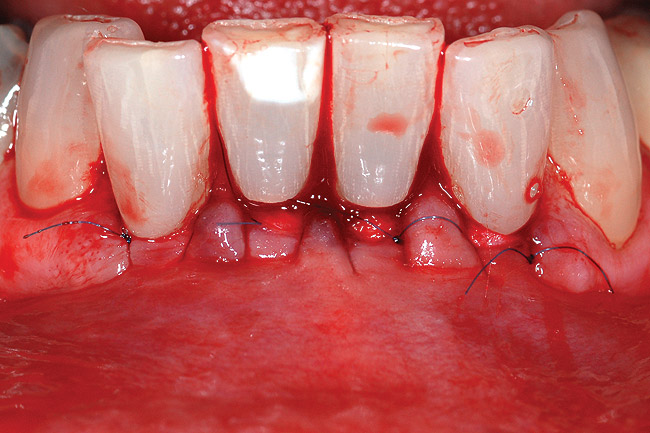

Fig 8 and Fig 9. Non-carious cervical lesions of moderate depth, Miller Class III gingival recession, absence of attached gingiva, shallow vestibule, and extrusion of the central incisors.

Fig 10 and Fig 11. The irregular root surface was smoothed.